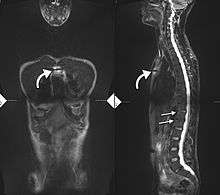

Radiographic features

- The earliest changes in the sacroiliac joints demonstrable by plain x–ray shows erosions and sclerosis.

- Progression of the erosions leads to pseudo-widening of the joint space and bony ankylosis.

- X-ray spine can reveal squaring of vertebrae with spine ossification with fibrous band run longitudinally called syndesmophyte while producing bamboo spine appearance.

- A drawback of X-ray diagnosis is the signs and symptoms of AS have usually been established as long as 8–10 years prior to X-ray-evident changes occurring on a plain film X-ray, which means a delay of as long as 10 years before adequate therapies can be introduced. Options for earlier diagnosis are tomography and MRI of the sacroiliac joints, but the reliability of these tests is still unclear.

-

Lateral X-ray of the mid back in ankylosing spondylitis

Lateral X-ray of the neck in ankylosing spondylitis

X-ray showing bamboo spine in a person with ankylosing spondylitis.

CT scan showing Bamboo spine in ankylosing spondylitis

T1-weighted MRI with fat suppression after administration of gadolinium contrast showing sacroiliitis in a patient with ankylosing spondylitis